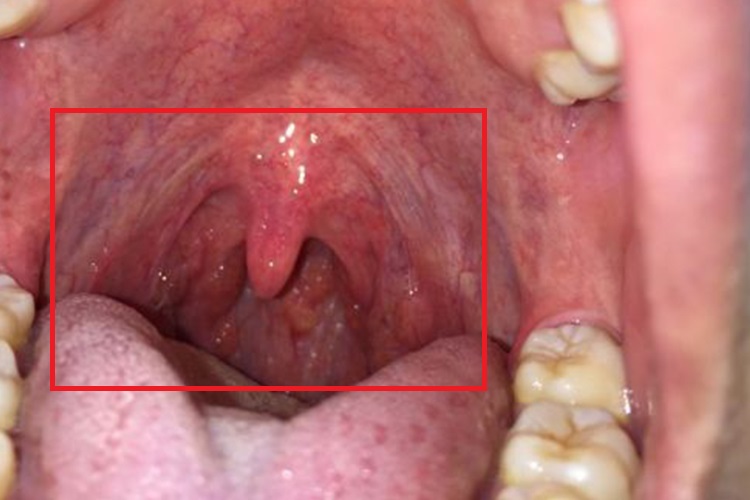

咽炎滤泡增生通常能治好,但需要积极配合医生进行处理,比如去除诱因、药物治疗等。作为慢性咽炎的一种常见表现,可能会诱发咽部异物感、干燥感、刺激性咳嗽等不适症状,在治疗之后,可以有效改善病情,帮助缓解不适。

3、物理治疗:通过微波、激光等物理疗法对滤泡进行局部照射,可以使病情逐渐消退。这些治疗方法具有微创、疗效显著的特点,能够快速缓解症状,提高患者的生活质量。

5、手术治疗:对于保守治疗效果不理想的患者,可以考虑手术治疗。手术方式包括等离子射频消融术、冷冻术等,手术可以烧灼过度增生的咽喉壁淋巴滤泡,从而治疗疾病。